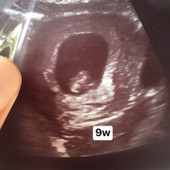

9 สัปดาห์ ได้ยินเสียงหัวใจแล้ว

ทีมพฤศจิกายน 9 week แล้ว เจ้าก้อนแม๊🩷👼🏻.

ไปหาคุณหมอ ซาวด์ท้อง 9w4day ตอนนี้ 10w 2day แล้วค่ะ น้องแข็งแรงมากๆ ได้ยินเสียงหัวใจน้องแล้วค่ะ ดีใจมากๆ ท้อวแรกด้วยค่า

9wเหมือนกันค่ะ น้องมีหัวใจเต้นแล้ว มีแขนจิ๋วๆ ตอนนี้ได้11w5dแล้วค่ะ ขอให้น้องแข็งแรงนะคะ

ทางนี้ 9W5d หมอบอกเสียงหัวใจน้องดีค่ะ 🥰